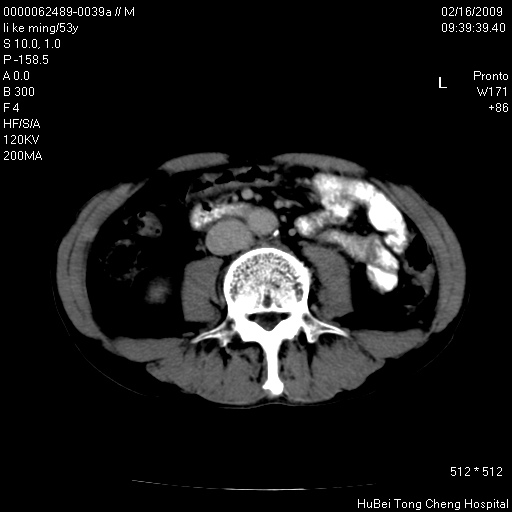

以下是引用卜一在2009-2-16 16:13:00的发言:[br]胰胆管扩张,末端明显狭窄 梗阻,胰头及十二指降段壶腹部结构紊乱。多考虑:十二指降段壶腹部癌!

以下是引用zsl6918在2009-2-17 8:48:00的发言:[br]符合胰头癌侵犯十二指肠。